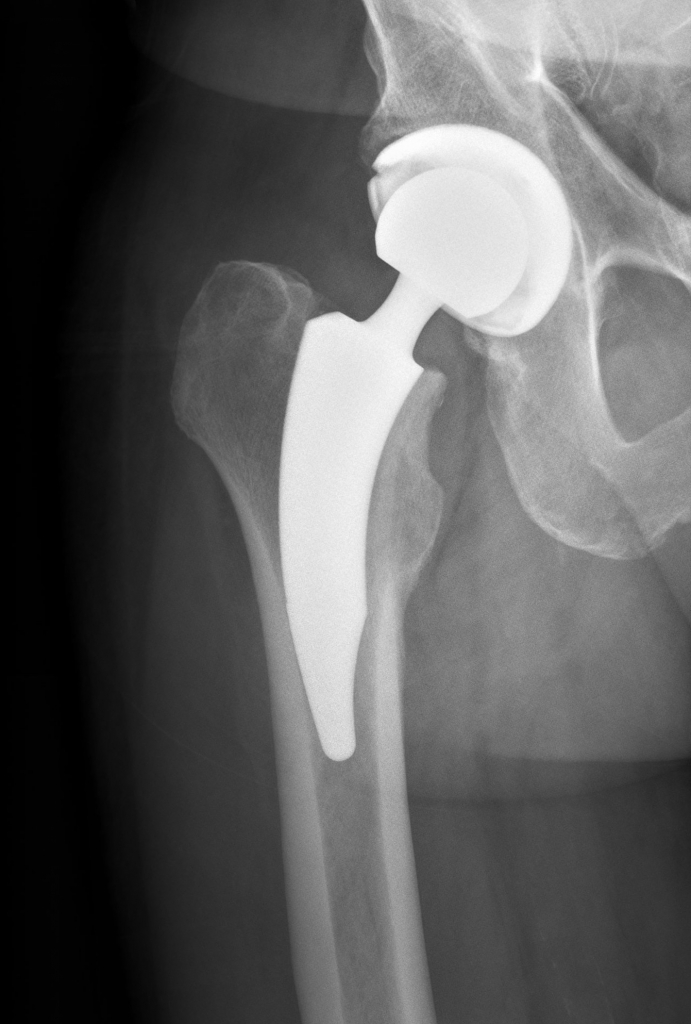

Unter dem Begriff Hüftprothese versteht man den vollständigen Ersatz (Totalendoprothese) des eigenen Hüftgelenkes. Es wird sowohl die eigene Gelenkspfanne, als auch der Oberschenkelkopf inklusive Oberschenkelhals mittels Metallimplantat ersetzt.

Im Inneren einer Hüftprothese sorgt das Innenleben (Gleitpaarung) für eine reibungsarme Verbindung. Es kommen hier entweder Keramiken oder Kunststoffe zum Einsatz, die die Langlebigkeit einer Hüftprothese ermöglichen.

AUFBAU EINES KÜNSTLICHEN HÜFTGELENKES

Bei der Implantation eines Kunstgelenkes wird das arthrotisch veränderte Hüftgelenk komplett ersetzt. Der Oberschenkelhals wird künstlich durchtrennt und der Oberschenkelkopf auss der Gelenkspfanne entfernt. Danach wird in die natürliche Hüftpfanne eine Metallpfanne eingesetzt und im Bereich des Oberschenkels ein Metallschaft eingeführt. Zwischen den Metallkomponenten dient ein abriebsarmer Kunststoff (Polyethylen) oder Keramik in Kombination mit einem Keramikkopf als Gleitschicht in der Kunstpfanne.

Die beiden Metallkomponenten bestehen hauptsächlich aus Titan und können spezielle Beschichtungen aufweisen. Einerseits hilft eine Calciumphosphat-Beschichtung der schnellen Osteointegration, also dem Einwachsen des Implantates in den Knochen, anderseits dient eine Plasmaspraybeschichtung der primären Stabilität nach der Operation und der besseren Verbindung mit dem Knochen.

Bild oben: Prothese mit normaler Schaftlänge zur Verankerung im Röhrenknochen

Bild unten: Kurzschaftprothese mit Verankerung im Schenkelhals